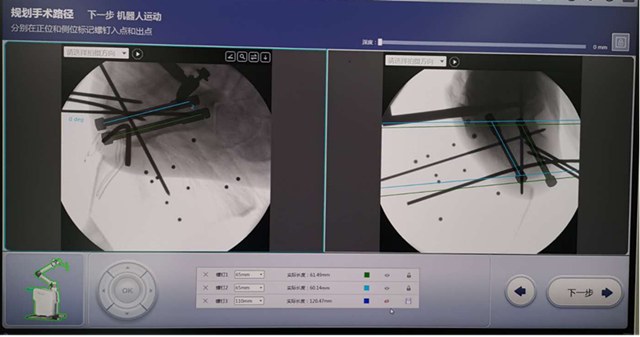

近期,兰大二院足踝外科学组副主任医师王凯在汪玉良、刘京升主任指导下,利用骨科人工智能机器人完成一例复杂跟骨骨折手术,目前该技术尚属省内首例。

患者,男,27岁,跟骨粉碎性骨折,入院时右足明显肿痛,这种情况下,传统手术需要顾及患者皮肤条件及软组织情况,待患者肿胀消退后才能行手术治疗,一般病程需两周左右,且手术效果差,对周围关节影响较大。通过人工智能机器人导航技术手术,实现了精准医疗及术后早期康复的目的,既缩短了住院时间也减轻了患者经济负担,手术效果理想。

跟骨骨折骨折类型复杂多样,手术并发症发生率高,致残率高,严重影响患者的生活。将微创理念和人工智能机器人技术结合应用于跟骨骨折,旨在减少传统手术后所出现的伤口或软组织相关并发症的发生率,又能准确复位和固定骨折。该例手术的顺利实施,标志着我院骨科在足踝及创伤领域已达到省内领先水平,至此我院骨科已在创伤、关节、脊柱、足踝等多方面同步开启了人工智能时代!